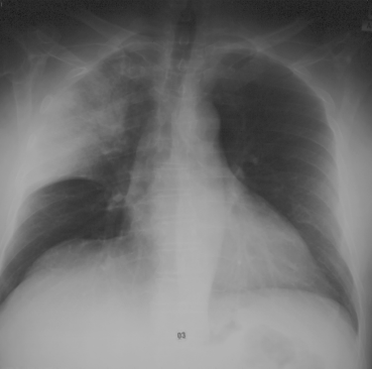

Syndrome alvéolaire :

• opacités systématisées

• à limites floues

• avec un bronchogramme aérique

• confluentes

• dʼévolutivité rapide